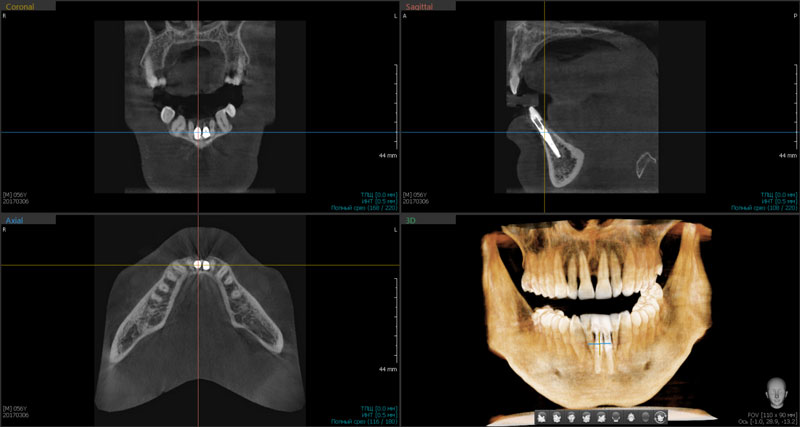

Рис. 6 Дентальная объемная томограмма после проведения одномоментной имплантации в проекции 31,41 зубов. Инклинация имплантатов корректна

Обязательной тактикой немедленной имплантации следует считать атравматичную экстракцию зубов во фронтальном отделе, которая производится с помощью тонких элеваторов. Осуществление люксации при данном оперативном подходе возможно только   с медиальной, дистальной и оральной стенок альвеолы во избежание перфорации вестибулярной стенки апикальной частью имплантата (Рис.1). Даже при остеоинтеграции имплантата при повреждении вестибулярной стенки эстетика будет нарушена. Поэтому после проведения немедленной имплантации 3D-томография снова является идентификатором показателей инклинации имплантата, глубины его погружения в губчатый слой, выявления дефектов костной структуры (Рис.2,3,4,5,6).

Следует выделить кросс-секции, которые обеспечивают полную ясность при анализе, моделировании виртуального имплантата, проверке корректности его установки, выделяя важные показатели клинического случая: градус наклона, визуализация качества эндодонтического лечения соседних зубов (Рис.7).

Рис.7 Кросс-секции для выявления градуса наклона имплантатов в области 31,41 зубов при первичной стабильности. Инклинация имплантатов корректна